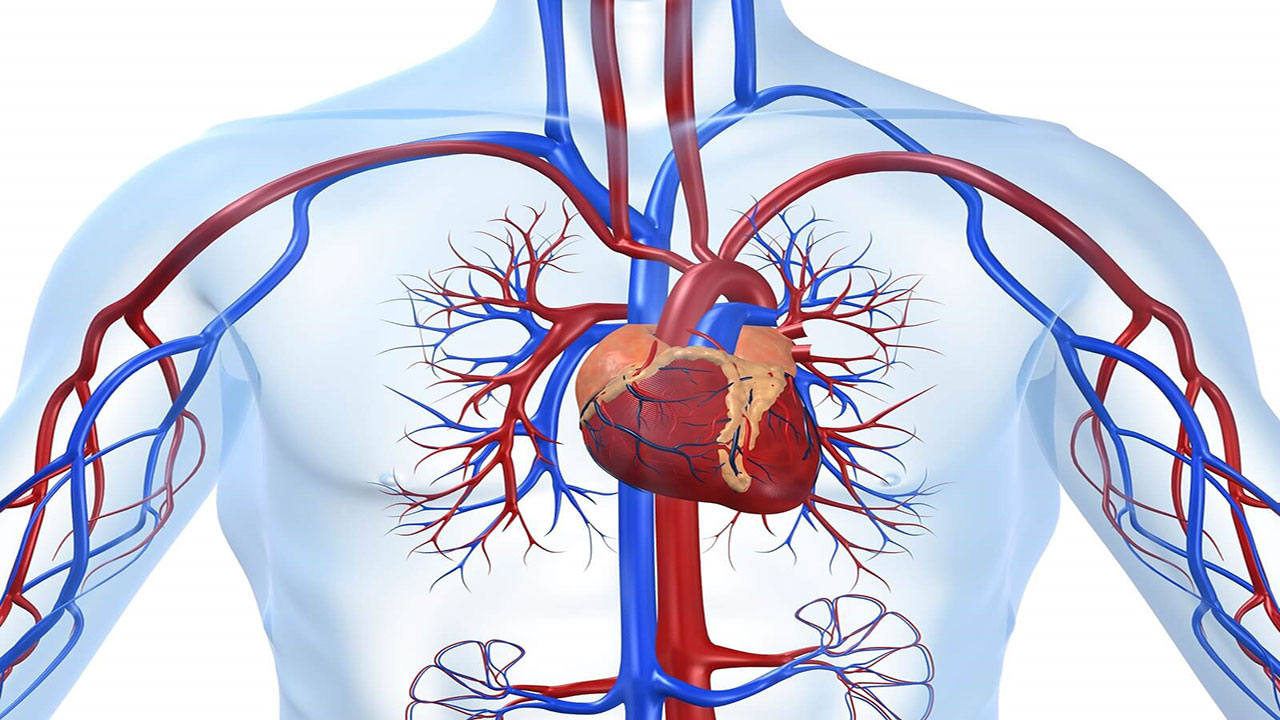

قیمت: 88٬000 تومان - دسته بندی فایل: پاورپوینتپاورپوینت فیزیولوژی قلب و دستگاه گردش خون

فروش ویژه پاورپوینت حرفه ای فیزیولوژی قلب و دستگاه گردش خون با تخفیف استثنایی فقط 124 هزار تومان تعداد اسلاید: 51 اسلاید